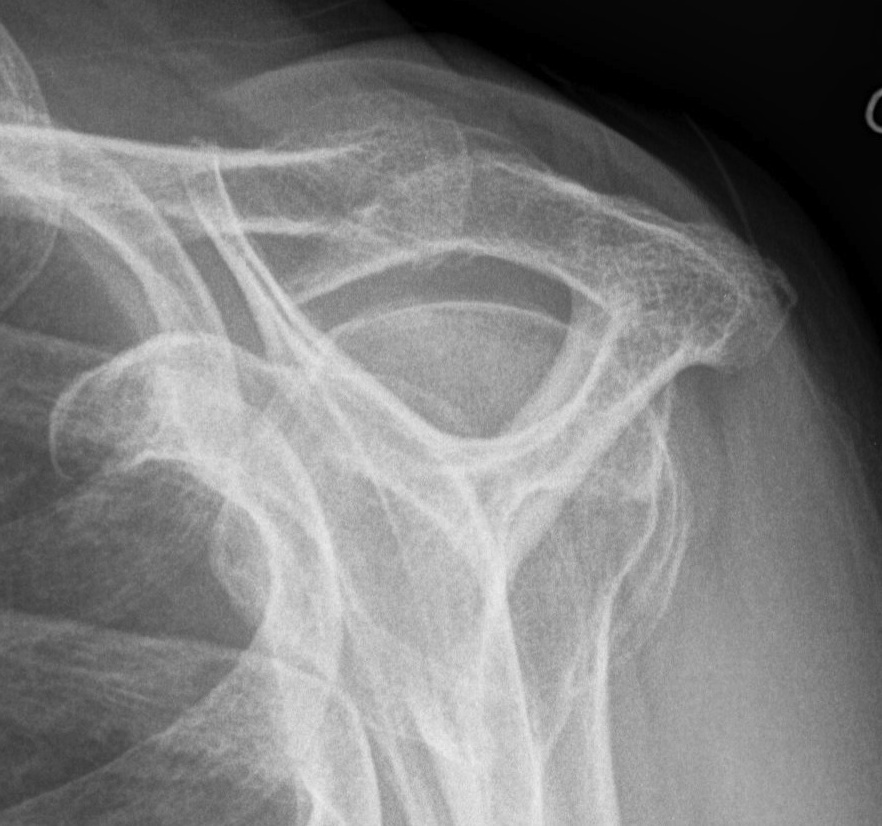

Xray

Look for: acromial morphology / high riding humeral head / rotator cuff arthropathy

Acromial spur / superior migration humeral head / rotator cuff arthropathy